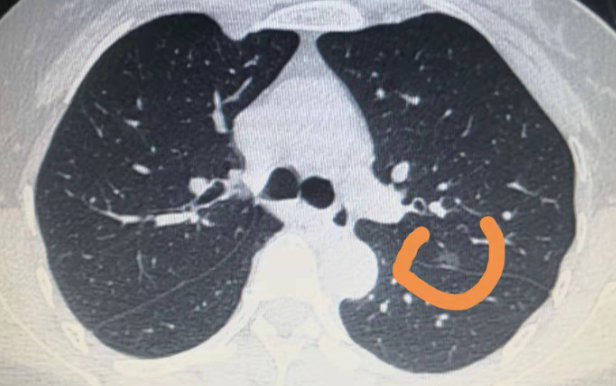

近年来,随着CT扫描技术的进一步提升以及计算机辅助诊断(CAD)软件的应用,肺结节的检查出概率正在日益提升,通常是在体检进行胸片检查或者胸部CT检查的时候发现肺部结节。随着肺癌发病率的迅速上升,根据详细统计肺癌已占到肺部结节的一半以上,因此对于体检时发现的肺内结节绝不能忽视。